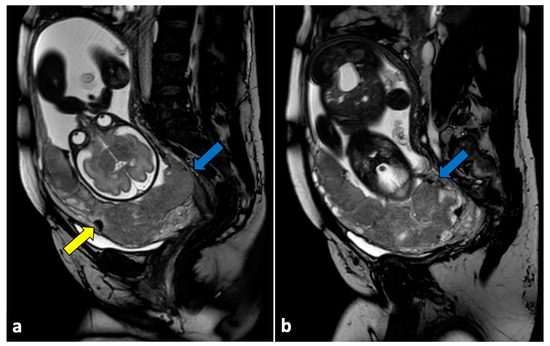

The Diagnostic Accuracy of Magnetic Resonance Imaging for Maternal Acute Adnexal Torsion during Pregnancy: Single-Institution Clinical Performance Review

by Jong Hwa Lee, Hyun Jin Roh, Jun Woo Ahn, Jeong Sook Kim, Jin Young Choi, Soo-Jeong Lee and Sang Hun Lee

J. Clin. Med. 2020, 9(7), 2209; https://doi.org/10.3390/jcm9072209 - 13 Jul 2020

Cited by 15 | Viewed by 6784

Background: For acute adnexal torsion of pregnant women, appropriate treatment based on an accurate diagnosis is especially important for fertility preservation and timely treatment. The 2017 American College of Obstetricians and Gynecologists (ACOG) Committee Opinion No. 723 announced its practice-changing guidelines to ensure [...] Read more.

Background: For acute adnexal torsion of pregnant women, appropriate treatment based on an accurate diagnosis is especially important for fertility preservation and timely treatment. The 2017 American College of Obstetricians and Gynecologists (ACOG) Committee Opinion No. 723 announced its practice-changing guidelines to ensure that diagnostic magnetic resonance imaging (MRI) conducted during the first trimester and gadolinium exposure at any time during pregnancy are safe for fetal stability. Unfortunately, few studies have been performed to evaluate the usefulness of the diagnostic accuracy of MRI for acute adnexal torsion during pregnancy. Objective: We sought to determine the efficacy of diagnostic MRI modality using multiparameter for maternal adnexal torsion during pregnancy. Methods: From 1 January 2007 to 31 January 2019, 131 pregnant with MRI tests were reviewed. In this retrospective cohort study, 94 women were excluded due to conditions other than an adnexal mass, and 37 were identified through MRI analyses conducted before surgery for suspected adnexal torsion. The primary outcome was the diagnostic accuracy of sonography and MRI, and the secondary outcome was the usefulness of Apparent diffusion coefficient (ADC) values for predicting the severity of hemorrhagic infarction between the medulla and cortex of the torsed ovarian parenchyma. Results: Our study demonstrates that in the diagnosis of adnexal torsion during pregnancy, the sensitivity, specificity, positive predictive value, and negative predictive value are 62.5%, 83.3%, 90.9%, and 45.5% for sonography and 100%, 77.8%, 90.5%, and 100% for MRI. MRI results in surgical-proven adnexal torsion patients revealed unilocular ovarian cysts (36.8% (7/19)), multilocular ovarian cysts (31.6% (6/19)), and near normal-appearing ovaries (31.6% (6/19)). Pathology in adnexal torsion revealed a corpus luteal ovarian cyst (63.2% (12/19)) and underlying adnexal pathology (46.8% (7/19)). Maternal adnexal torsion during pregnancy was more likely to occur in corpus luteal ovarian cysts than in underlying adnexal masses (odds ratio, 2.14; 95% confidence interval (CI), 0.428–10.738). MRI features for adnexal torsion were as follows: tubal wall thickness, 100% (19/19); ovarian stromal (medullary) edema, 100% (19/19); symmetrical or asymmetrical ovarian cystic wall, 100%(19/19); prominent follicles in the ovarian parenchyma periphery, 57.9% (11/19); periadenxal fat stranding, 84.2% (16/19); uterine deviation to the twisted side, 21.1% (4/19); and peritoneal fluid, 42.1% (8/19). The signal intensity of the ADC values of the ovarian medulla and cortex were compared between the cystectomy and detorsion (CD) and salpingo-oophorectomy (SO) groups. The ADC values of the CD and SO groups were 1.81 ± 0.09 × 10−3 mm2/s and 1.91 ± 0.18 × 10−3 mm2/s, respectively (P = 0.209), in the ovarian medulla and 1.37 ± 0.32 × 10−3 mm2/s and 0.96 ± 0.36 × 10−3 mm2/s, respectively (P = 0.022), in the ovarian cortex. The optimal cut-off value of ADC values for predictable total necrosis in the torsed ovarian cortex was ≤ 1.31 × 10−3 mm2/s (area under the curve (AUC) = 0.81; 95% CI 0.611–1.0; P = 0.028). Conclusion: Our data showed that maternal adnexal torsion during pregnancy occurred in most corpus luteal cystic ovary cases and some normal-appearing ovary during the 1st and 2nd trimesters of gestation. Therefore, this study is the first study to elaborate on the existence or usefulness of the diagnostic MRI for acute maternal adnexal torsion during pregnancy and to provide a predictive diagnosis of the severity of hemorrhagic infarction for deciding surgical radicality. Full article